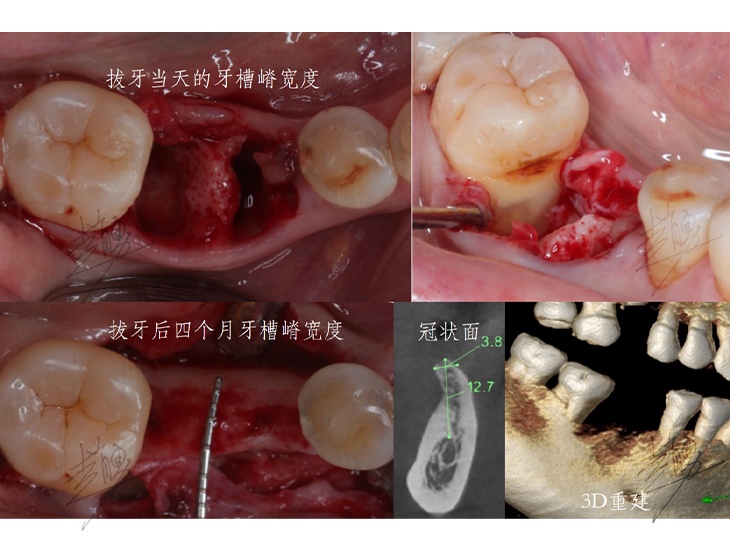

针对后牙缺失患者,于拔牙同期行位点保存术,4 个月后复查牙槽嵴宽度稳定,骨量充足,为后续种植修复奠定良好骨条件。